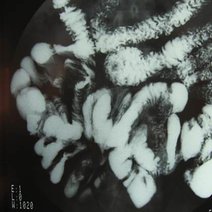

阑尾炎是什么

阑尾炎属于一种感染性疾病,由于阑尾是个盲端,粪石很容易堵塞在阑尾的管腔之内,就会导致腔内压力进行性的增高,继发了感染,病人会表现为发热以及疼痛。典型的症状...33662人收听

阑尾炎是腹部外科最常见的一种急腹症,阑尾炎的发生与免疫力低下、阑尾管腔的粪石堵塞或食物残渣的堵塞有关,阑尾炎手术多采取腹腔镜阑尾切除术,达到创伤小,痛苦...94859人收听

阑尾炎,顾名思义就是阑尾发生炎症的疾病,阑尾炎是普外科最为常见的急腹症。 1.阑尾炎发生炎症是由于其自身解剖特点决定的,解剖结果为细长盲管,腔内富含微生物,肠...5683人收听